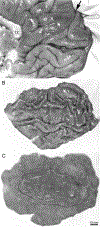

In some mammalian species, geniculocortical afferents serving each eye are segregated in layer 4C of striate cortex into stripes called ocular dominance columns. Having described the complete pattern of ocular dominance columns in the human brain, the authors enumerate here the principal enigmas that confront future investigators. Probably the overarching challenge is to explain the function, if any, of ocular dominance columns and why they are present in some species and not others. A satisfactory solution must account for the enormous natural variation, even within the same species, among individuals in column expression, pattern, periodicity, and alignment with other components of the functional architecture. Another major priority is to explain the development of ocular dominance columns. It has been established clearly that they form without visual experience, but the innate signals that guide their segregation and maturation are unknown. Experiments addressing the role of spontaneous retinal activity have yielded contradictory data. These studies must be reconciled, to pave the way for new insights into how columnar structure is generated in the cerebral cortex.